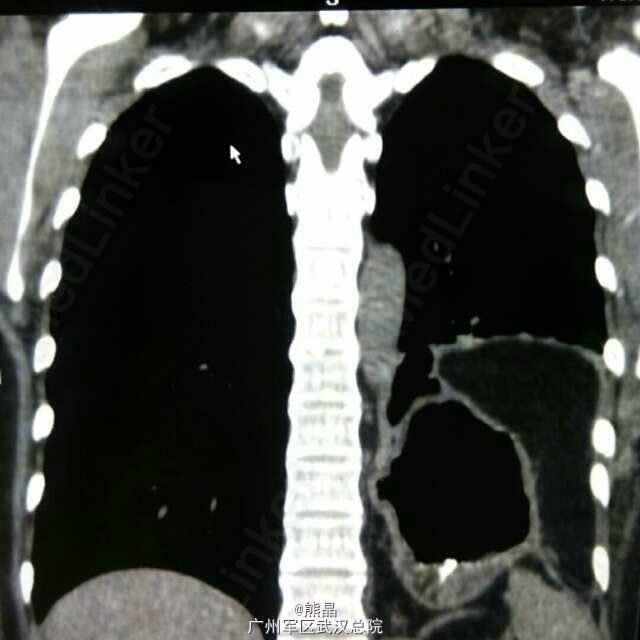

食管憩室术后

食管憩室

此病例为县医院食管憩室手术后病人,来本院做钡餐,钡餐是我做的,高度怀疑膈疝,后做了CT三维确诊。 大家可以看看图,哪里有不明白的可以问我。